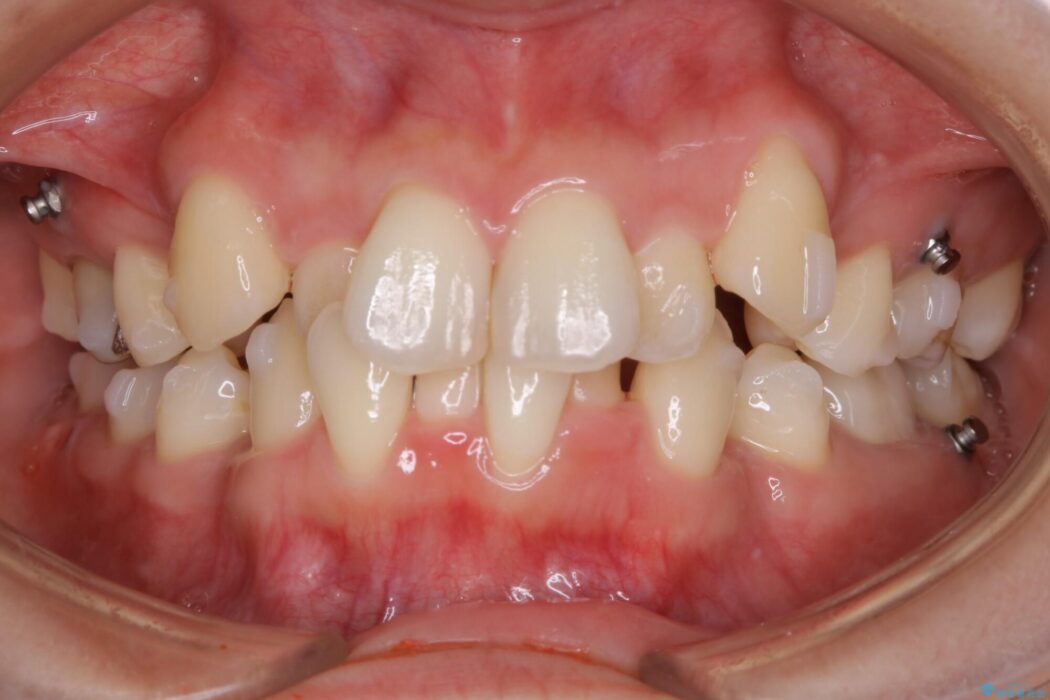

左右の奥歯が前方に寄っていることにより八重歯の発生や重度の叢生に繋がっていました。

まず噛み合わせに問題が少ない奥歯の位置を極力変えないように上下左右4番目の歯を抜歯することで歯列矯正のためのスペースを確保し、空いた隙間で前歯の凹凸をきれいに並べていくこととしました。

また、ご要望がありマイクロインプラント治療もしています。